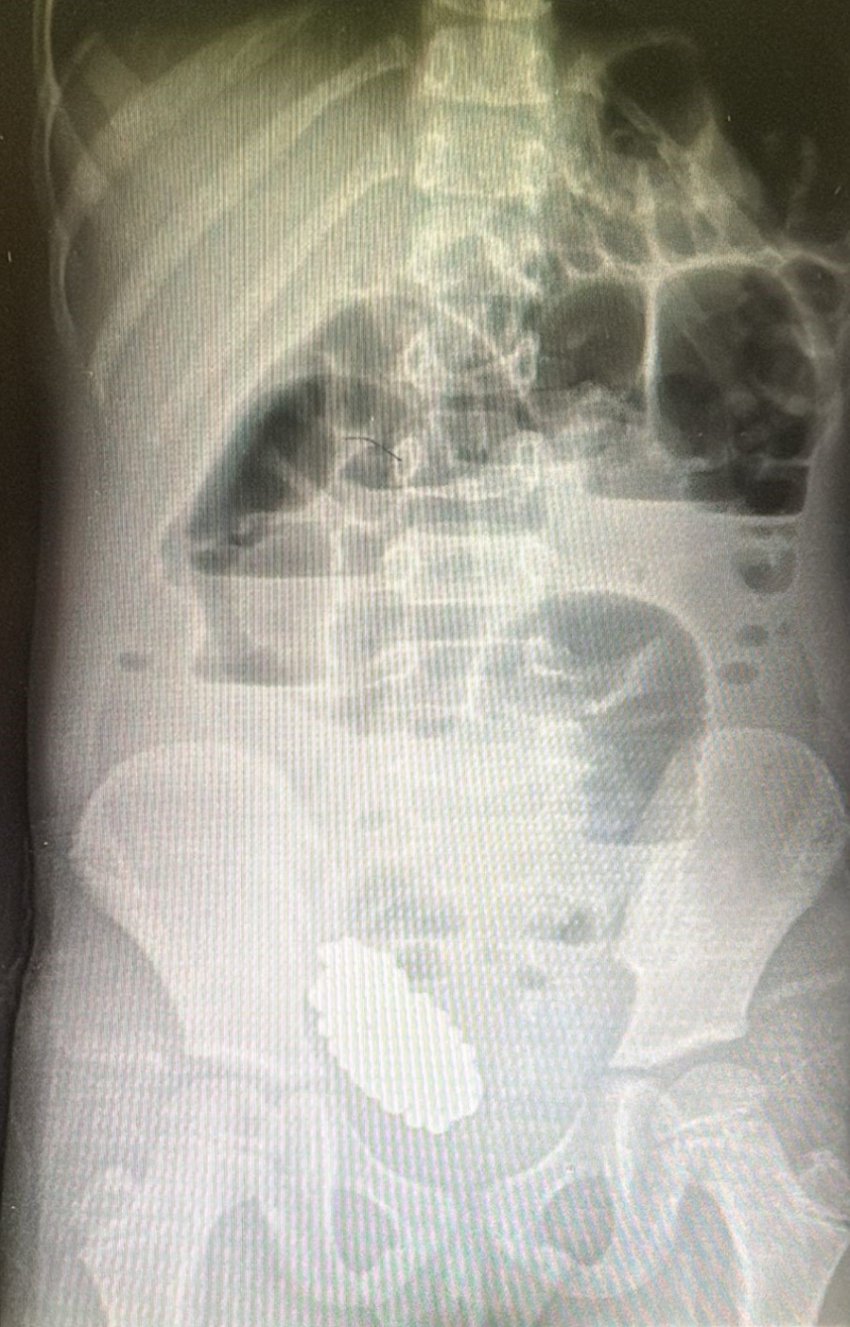

Обследование выявило кишечную непроходимость, вызванную инородными телами. Как выяснилось, магнитные шарики, проглоченные девочкой, слиплись в единый конгломерат, вызвав сдавление стенки кишечника и нарушение его функций.

Родители признались, что не сразу поняли причину недомогания дочери. Только после рентгенологического исследования они вспомнили, что ранее в доме пропала игрушка с магнитными элементами, купленная для старшего брата.

В ходе лапароскопической операции, которая прошла успешно, хирургам удалось извлечь все 134 магнитных шарика.